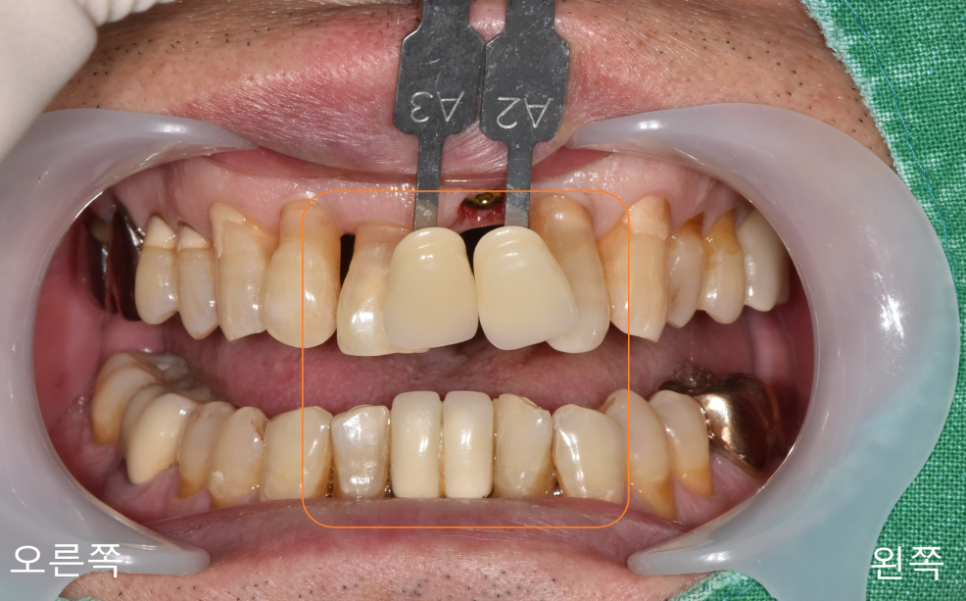

나이 성별 상관없이

앞니의 경우 치아 모양과 색을

중요하게 생각하게 되는데요.

전문가가 색을 확인하여도 결국 환자분의 마음에 들지 않으면

만족도가 떨어질 수밖에 없습니다.

앞니의 경우 거울을 볼 때도 가장 먼저 보이고

상대방이랑 말할 때도 많이 보이기 때문이죠.

서울 바르디 치과에서는 치아 색 가이드를 통해

사진도 찍고 환자분과 소통하여

최대한 만족을 드릴 수 있도록

제작하여 드립니다.